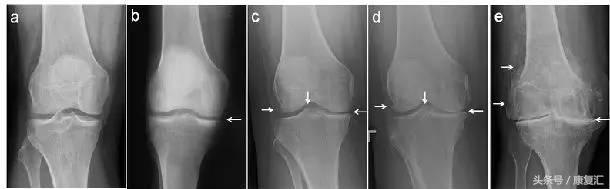

生活中,偶尔感觉自己“关节肿痛”,去医院检查,发现不是得了“滑膜炎”(图1 a,b),要么就是“骨质增生”(图1 c,d,e),或者还有“关节炎”(图1 d,e)。那么,这几种疾病具体是什么?请随小编一探究竟。

图1. 膝关节X片

从上可见,早期的(骨)关节炎就是滑膜炎。因为在常规X线片上无法观察到明显的关节周围骨质增生(即骨赘形成),或关节间隙变窄(图1c,d,e),因此被称之为“滑膜炎”。

患者感觉关节疼痛时候,去医院拍片检查,报告“骨质增生”,并在X光片中观察到股骨或胫骨关节的周缘或髁间棘处有骨质增生(图1c,d,e,左侧和中间白箭),因此判断自己患上了“骨质增生”(骨刺)。

“滑膜炎”就是关节磨损的轻度表现,“退行性骨关节炎”就是随着年龄增大以及关节磨损的重度表现,即诊断中常见的“关节炎”(图1c,d,e)。

关节在夜晚尤其疼痛难耐的,甚至由于关节痛无法行走外出的患者(图1e),应进行关节置换手术,以便早日恢复。